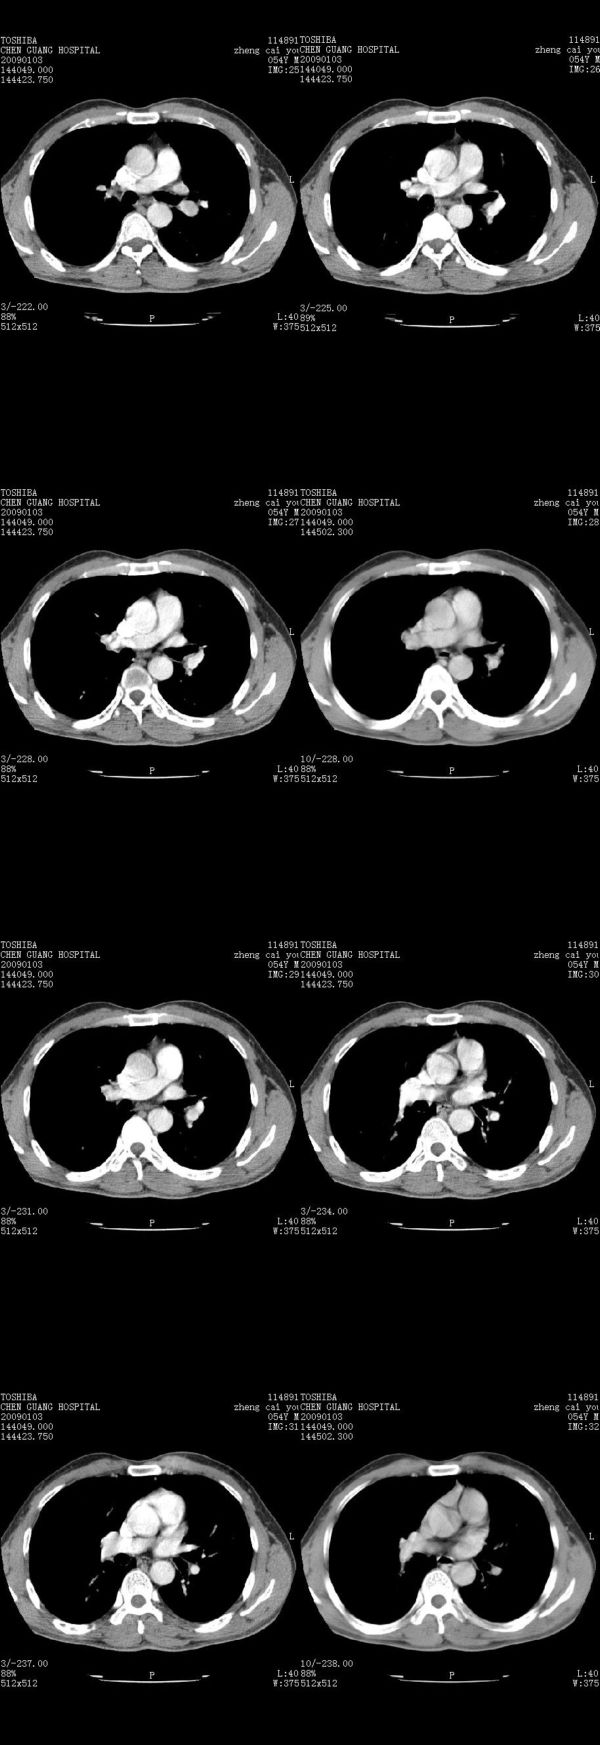

男,54岁,右侧胸部疼痛,平时吸烟,有抽烟后咳嗽咯痰史。昨天没把xiphoid软件吃懂,所以没把纵隔窗图像处理出来!请各位老师帮忙看一下右肺门有没有问题?谢谢!!!!!!!!!!

右肺上叶后段近气管旁仍可见一结节灶,不除外为肿大的淋巴结影。

气管前腔静脉后似见增大淋巴结影,肺门区未见明显肿块影。肺窗示右肺中叶外侧段透亮度增高,可过一段时间再查一下对比一下,毕竟是自己的至亲,又有条件,辐射就顾不得了。

也觉得还好吧,只是右下肺动脉显粗了点,纵膈有钙化淋巴结,再有肺窗就更好了

各位老师:奇静脉增宽,肺上未见明显实变,这还需注意观察些什么?????

右侧肺门影增大,不除外增大淋巴结可能

上腔静脉后淋巴结影,不知道最后结果怎么样?